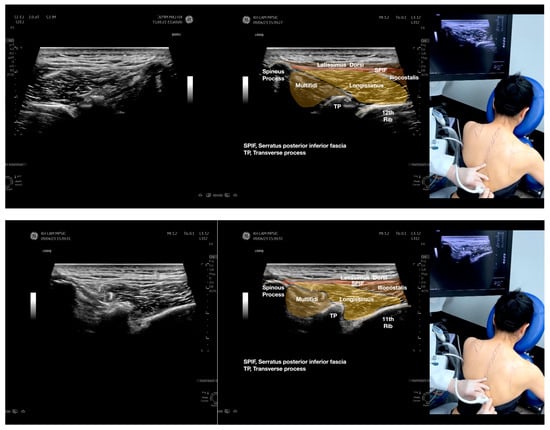

Sonoanatomy of the lateral border of the inferior trapezius, its related muscles, and the infraspinatus fascia. The step-by-step scanning techniques of the structures illustrated in this figure have been shown in Video S6. Available online: https://www.dropbox.com/s/vjj49wiwdsidouz/Figure%202.docx?dl=0 (accessed on 1 January 2023). Dynamic ultrasound scanning of the anterior shoulder with the humerus externally rotated (palm up), elbow straight, and the shoulder actively flexed and abducted at about 90 to 100 degrees shows that the fibrotic and thickened bursa was noted to be snapping between the subscapularis tendon and the coracoacromial ligament, as shown in Video S3. The patient noticed this snapping during many of his daily activities with his shoulder flexed just above 90 degrees, e.g., taking off clothes and combing hair. Ultrasound-guided injection of the thickened and fibrotic bursa did not reproduce the usual pain nor reduce the pain, and it did not improve the shoulder snapping and flexion power with the elbow straight, shoulder flexed to 90°, and the humerus externally rotated (palm up). Ultrasound-guided injection of the cortical break reproduced the concordant pain and temporarily and partially reduced the pain with snapping and residual anterior shoulder pain (Video S4), but it did not change the snapping or weakness in the right shoulder flexion with the humerus in external rotation. With the failure of direct anterior treatment to the suspected lesions, it was essential to further explore other causes for the anterior painful snapping. Further detailed musculoskeletal examination of the scapular movement showed that the right scapulothoracic movements were not smooth compared to the left counterpart (Video S5) [4,5]. There might be some disruptions in the right infraspinatus fascia (IF) and its related muscles, including the lateral edge of the right inferior trapezius, rhomboid minor and major [6], teres major, latissimus dorsi [7,8] (LD), and posterior deltoid attachments to the IF [9,10]. Clinically, prominent and active trigger points were observed in the right infraspinatus muscle. Holding the inferior angle of the scapula, with the examiner’s fingers, especially over the origin of the teres major muscle over the scapula, the latissimus dorsi [11,12,13] and the scapular insertion of the rhomboid major muscle significantly improved the power of the resisted shoulder flexion with the elbow straight and the shoulder flexed to 90° with the humerus externally rotated (palm up). In order to illustrate the utilization of ultrasound-guided sonopalpation and ultrasound-guided digital palpation for detecting the suspected lesions of the IF and its related muscles, we presented the following videos (Videos S6–S9) and still images (Figure 2, Figure 3, Figure 4 and Figure 5) to demonstrate the essential techniques and crucial points of getting the normal sonoanatomy of the IF and its related structures. The gross anatomy of the IF and its related muscles were also shown in Figure 6, Figure 7 and Figure 8.